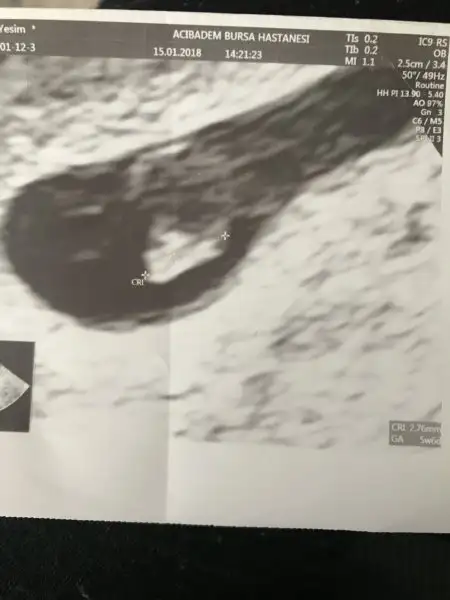

Ara canım mutlaka,vajinal kullanmak çok daha rahat. Dün sana kese fotosu koyacaktım dışardayım diye koyamadım. Şimdi koyayım bak. 1. Foto kesenin ilk hali, 2. Foto fasulyeye dönmüş hali.

Ben Eskişehir Acıbademde yaptırıcam takip ve doğumumu. Burada aşılamamı yapan doktorum var ona gidicem. 120 tl idi aralıkta zam gelmiştir ocakta sezeryan doğumda 5000 tl imiş sanırım. İlk muayene için tüp bebek yaptırdığım Bursa Acıbademdeki dr çağırdı ilk muayene tedavi ücretine dahil değilmiş orada 350 tl vericez sonra burada devam